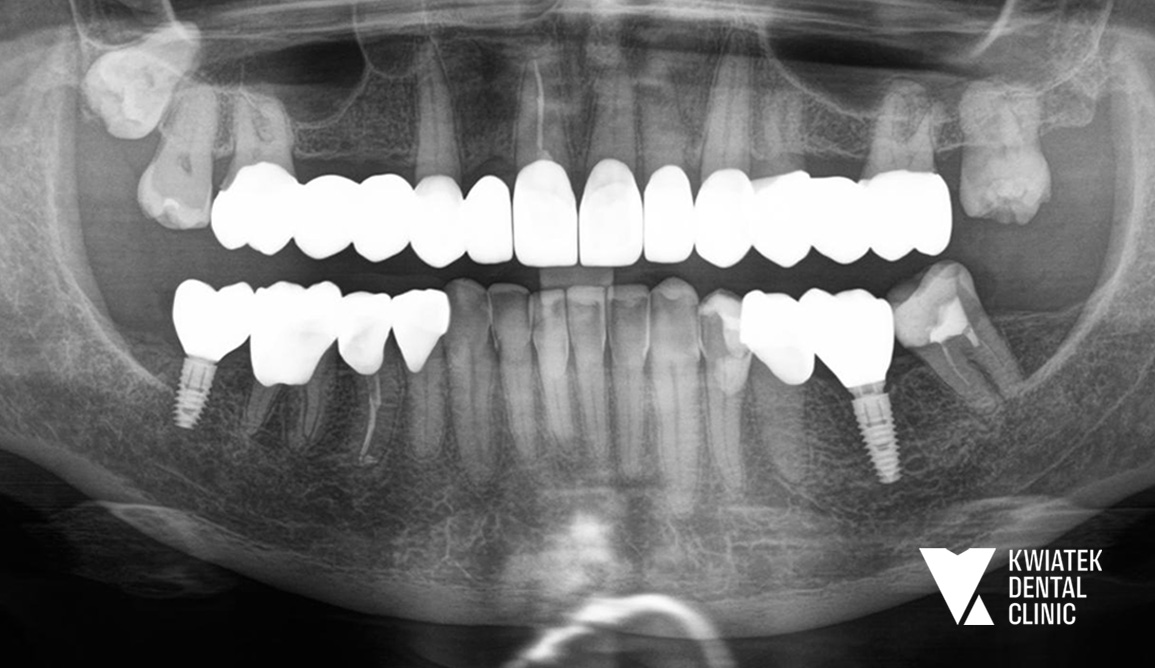

Kolejnym ważnym etapem była odbudowa brakujących zębów w odcinku bocznym żuchwy. Wykonano zabieg implantacji w pozycjach zębów 36 i 47 z użyciem systemu implantologicznego MIS C1 oraz z zastosowaniem szablonu chirurgicznego i nawigacji implantologicznej. Po zakończeniu procesu osteointegracji wykonano odbudowy protetyczne na implantach oraz korony protetyczne na zębach własnych Pacjentki. Równolegle przeprowadzono estetyczną rekonstrukcję zębów dolnych metodą flow injection, która pozwoliła na odbudowę ich kształtu i przywrócenie prawidłowych proporcji uśmiechu. Całość leczenia uzupełniono zabiegiem wybielania zębów metodą gabinetową z zastosowaniem systemu Philips Zoom.

Efektem leczenia jest kompleksowa odbudowa zdrowia jamy ustnej oraz harmonijna poprawa estetyki uśmiechu Pacjentki. Usunięto ognisko infekcji, odbudowano brakujące zęby z wykorzystaniem implantów i przywrócono prawidłową funkcję zgryzu.